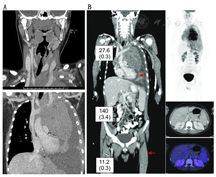

3.案例分析。用1个13岁患者的病例进一步说明多序列扫描方案。该患者在行颈部和胸部Dx CT扫描(图5A)及相应活组织检查(简称活检)后被诊断为淋巴母细胞淋巴瘤。为了完成分期,除腹部(骨盆)的Dx CT扫描外,患者还进行了躯干18F-FDG PET/CT显像。尽管辐射剂量已降低到合适的范围,笔者仍没有重复进行颈部和胸部Dx CT扫描,因为这些部位已经在最初诊断时完成了扫描。对患者进行了多序列PET/CT显像:先行颈部和胸部非Dx CT扫描,然后进行腹部和骨盆Dx CT扫描。另外进行的大腿以上部位非Dx CT扫描用于PET扫描时床位的解剖定位(图5B)。颈部和胸部的非Dx CT扫描不仅可以对同一区域更早进行的Dx CT扫描进行补充,还可以用于PET的衰减校正以及解剖定位。患者进行腹部(骨盆)Dx CT扫描的价值可经18F-FDG显像证实——右肾有18F-FDG低摄取灶,如果不进行对比增强Dx CT扫描显示该低衰减病变,则很难将其与18F-FDG的肾脏清除相区分。该转移性病变在非对比、非Dx CT图像上会显示不明显。非Dx CT扫描的区域,即颈部(胸部)及双下肢接受到的辐射剂量(0.3、0.3 mSv)明显低于进行标准Dx CT扫描的腹部(骨盆)区域的剂量(3.4 mSv)(图5B)。总体而言,本机构的多序列CT扫描方案的应用为临床医师提供了有价值的分期信息,同时降低了患者所受辐射剂量并节省了患者的时间。